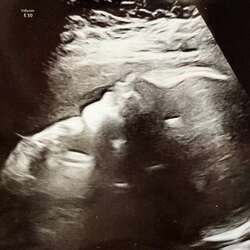

Helaas moet ik een curretage ondergaan, er zit nog een stuk weefsel van z'n 10x4.5 cm in mijn baarmoeder 😣.

Dit was mijn test afgelopen maandag, 13 december is mijn miskraam begonnen. Aanstaande maandag ga ik weer testen.